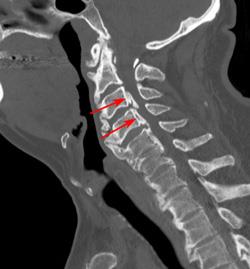

Computed tomography (CT) scans. More detailed than a plain X-ray, a CT scan can show narrowing of the spinal canal and can help your doctor determine whether you have developed bone spurs in your cervical spine.

CT scan showing narrowing of the spinal canal due to bone spurs

This CT scan shows bone spurs that have led to narrowing of the spinal canal (arrows).